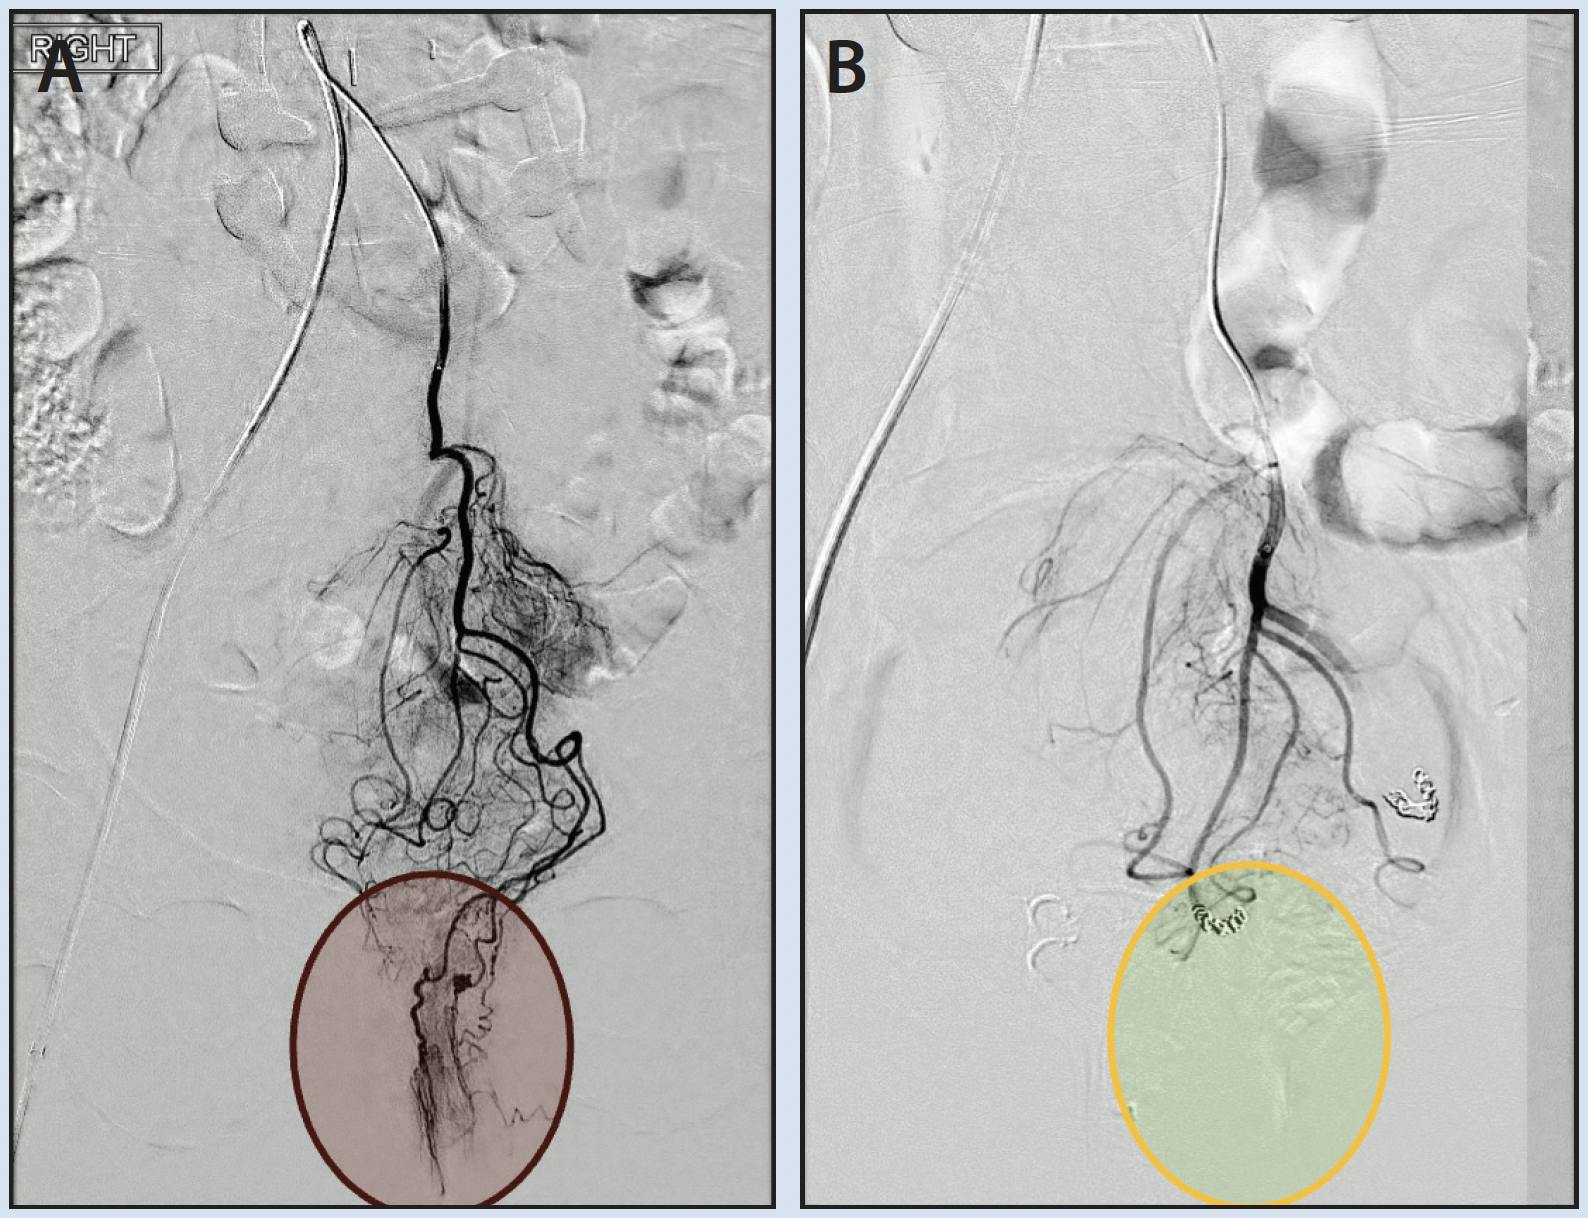

Arteriogram of the IMA demonstrated multiple dominant, hypertrophied SRA branches (Figure 1A). These terminal branches were selected and embolized using a combination of 800-µm particles and 2- to 3-mm coils. Final arteriography confirmed the absence of residual hyperemic blush (Figure 1B).

Figure 1. IMA arteriogram demonstrating multiple dominant, hypertrophied SRA branches supplying the corpus cavernosum recti. The hyperemic blush in the hemorrhoidal cushion region is circled in red (A). Final arteriogram following embolization of the dominant SRA branches using particles and coils. The image confirms the successful absence of residual hyperemic blush (circled in green) (B).